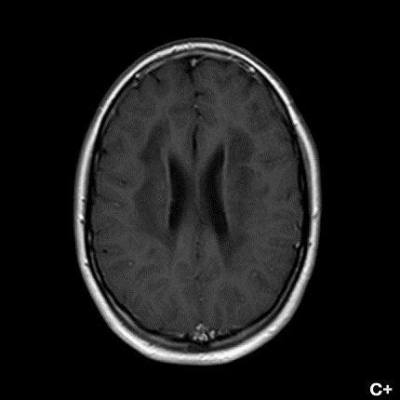

- B) Kontrastsız T1A serilerde tarifli alanlarda hipointens (oklar) görünüm izlendi. Kontrastlı T1A serilerde bu düzeyde (oklar) kontrastlanma artışı izlenmedi. Diffüzyon ağırlıklı serilerde belirgin diffüzyon kısıtlaması (oklar) görülmedi.

- Etkilenen bölgelerde T1’de hipointens, T2/FLAIR’da hiperintens sinyal değişiklikleri izlenir. DWI’de lezyonların periferinde kısıtlı difüzyon görülebilir. MRS’de beyaz cevherde laktat artışı saptanabilir, ancak bu her hastada mevcut değildir.